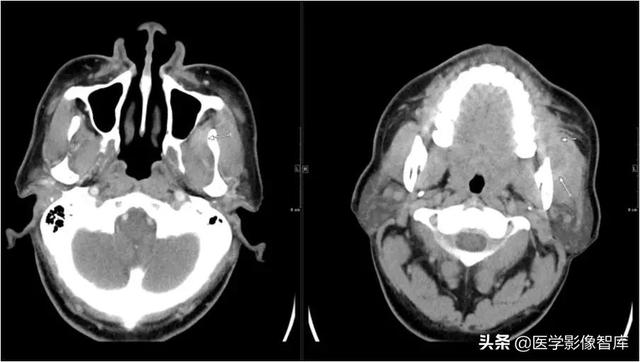

眶下间隙、颊间隙、咀嚼肌间隙、咽旁间隙

男,61岁,左侧面颊部、颌下、颏下肿胀15天,表面皮肤稍红,皮温不高,未扪及明显波动感。

角化囊肿并感染。